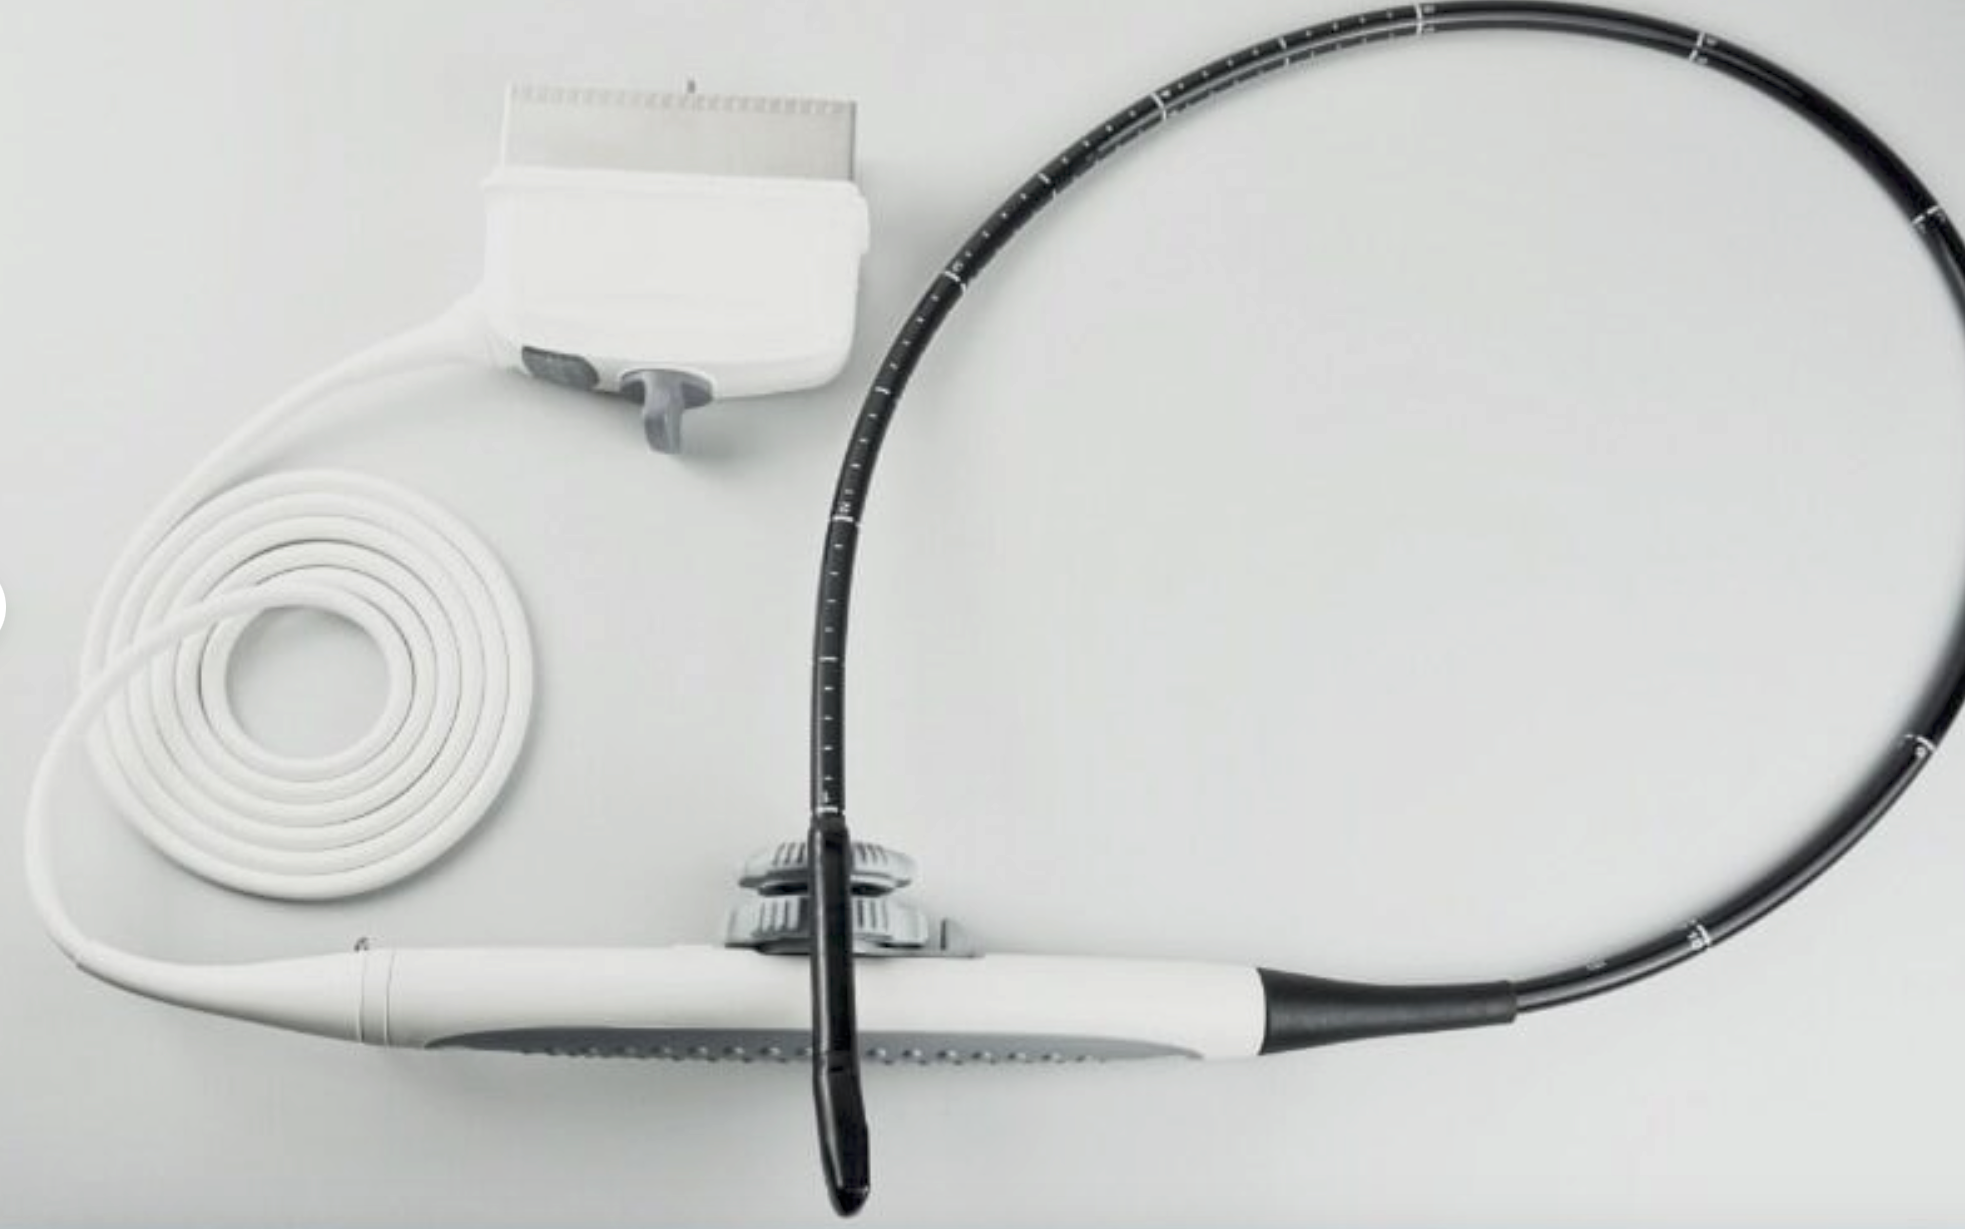

PHILIPS S5-1 SECTOR ARRAY ULTRASOUND PROBE

The Philips S5-1 Sector Array Ultrasound Probe is a high-performance imaging transducer designed for a range of clinical applications, including abdominal, cardiac, and obstetric/gynecological imaging. With a frequency range of 1-5 MHz, this probe offers excellent tissue penetration for deeper imaging, while maintaining high-resolution images for accurate diagnostics. The sector array design enables the probe to capture detailed images from a small footprint, making it ideal for patients with challenging body types or when accessing confined anatomical areas.

The Philips S5-1 probe is widely used for echocardiograms and other cardiovascular applications, as well as abdominal and obstetric exams. Known for its durability and reliability, it is compatible with Philips ultrasound systems and supports a variety of imaging modalities such as Doppler and 2D imaging. The S5-1 is designed for ease of use, providing clinicians with clear, real-time images to guide accurate diagnoses and treatment decisions.